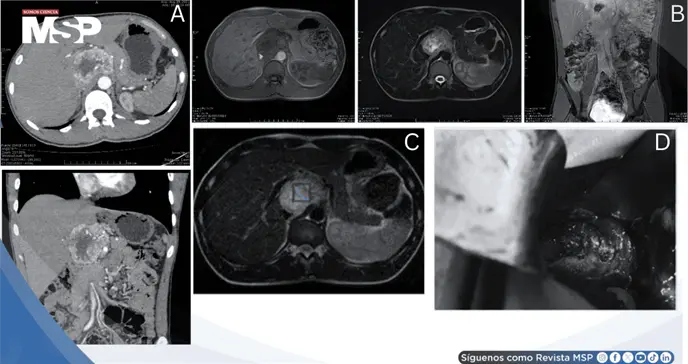

La tomografía computarizada contrastada demostró una masa bien definida de 7.2 × 6.5 × 5.4 cm, irregularmente esférica y heterogénea, con intenso realce arterial. Las imágenes axiales y coronales en fase arterial evidenciaron claramente su localización entre la vena porta y la vena cava inferior. Significativamente, no se observaron signos de invasión al lóbulo caudado hepático, páncreas, vena porta, vena cava inferior ni glándulas suprarrenales, hallazgos posteriormente confirmados quirúrgicamente.

La resonancia magnética con gadolinio mostró la lesión iso-hipointensa en T1, iso-hiperintensa en T2 y secuencias con saturación grasa, con realce intenso y heterogéneo tras el contraste. No se evidenciaron adenopatías regionales ni signos de invasión.

La espectroscopía por resonancia magnética de protones, técnica que evalúa la composición metabólica tumoral, no demostró el pico singlete característico de succinato a 2.42 ppm. La ausencia de este marcador descartó mutaciones en genes de succinato deshidrogenasa asociadas con comportamiento tumoral agresivo.